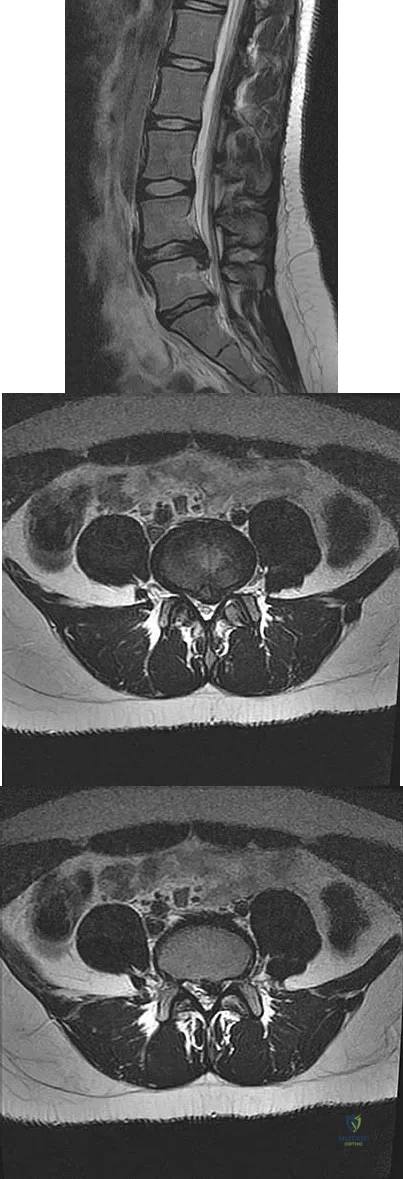

Question 53

A 50-year-old man with no history of trauma reports new-onset back pain after doing some yard work the previous day. He reports pain radiating down his leg posteriorly and into the first dorsal web space of his foot. MRI scans are shown in Figures 3a through 3c. What nerve root is affected?